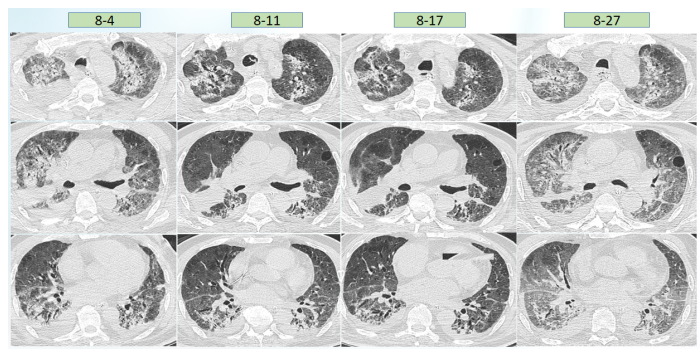

根据上述病原学结果,在7月28日患者出现发热后,考虑鲍曼不动杆菌感染可能性大,遂加用替加环素,患者体温下降,但至7月30日,患者体温再次升高,白细胞计数逐渐升高。结合气管镜和mNGS回报结果,考虑此时可能出现肺炎克雷伯菌感染,遂加用头孢他啶阿维巴坦,患者体温逐渐下降。8月4日ECMO撤机。患者撤离ECMO后,体温再次升高,考虑鲍曼不动杆菌感染,在原治疗方案基础上加用头孢哌酮舒巴坦(图7)。图7  患者体温及感染指标变化趋势(7月26日-8月8日)撤离ECMO后,复查患者胸部CT可见肺部病变控制较好,但8月27日发现患者肺部出现新的感染(图8)。加用头孢他啶阿维巴坦和头孢哌酮舒巴坦后,白细胞呈下降趋势,但患者体温仍不稳定,时有波动,遂联用多黏菌素(雾化),此后,患者白细胞逐渐趋于正常(图9)。图9  患者体温及白细胞计数变化趋势(8月9-22日)治疗回顾